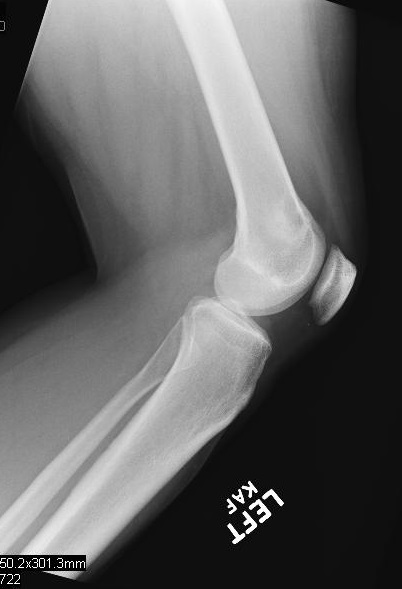

Plain x-ray

• Radiographs of low grade intraosseous osteosarcoma may demonstrate a benign appearance (Fig. 1 & 2).

• However, most lesions show intramedullary extension, cortical violation, and soft tissue involvement.

• The majority arise centrally in the bone, from the medullary cavity and more frequently are methaphyseal.

Fig. 2

Fig. 1 & 2: Plain X Ray of Low Grade Intraosseous Osteosarcoma. AP (Fig. 1) and Lateral (Fig. 2) view of the left knee, shows a mixed sclerotic-lytic lesion in the supracondylar area of the femur. There is no periosteal reaction, cortical destruction, or extraosseous soft tissue mass. The lesion is fairly well circumscribed with a sclerotic margin. The lesion deceptively looks benign